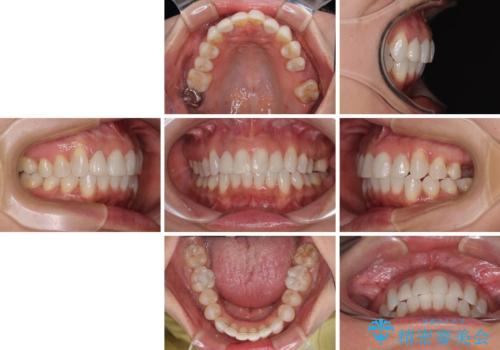

前歯のデコボコとむし歯治療の跡 インビザライン矯正とオールセラミッククラウン治療

- 前歯のセラミッククラウンの縁が見えることが気になってから、デコボコも気になるようになってきたとのことで来院された患者様です。

デコボコの程度は中等度であったため、インビザライン・モデレートパッケージにて歯列を整えることとしました。

セラミッククラウンの装着されていた前歯と、大きな修復治療の跡がある反対側の歯は、矯正治療後に補綴治療を行うこととしました。

奥歯の欠損はインプラント、ブリッジ、入れ歯のどれにすれば良いかを決められず、仕事が非常にお忙しいこともあり、保留としたまま治療を終えることとなりました。

後戻りのリスクがあるため、なるべく早めに欠損補綴治療を開始する予定です。